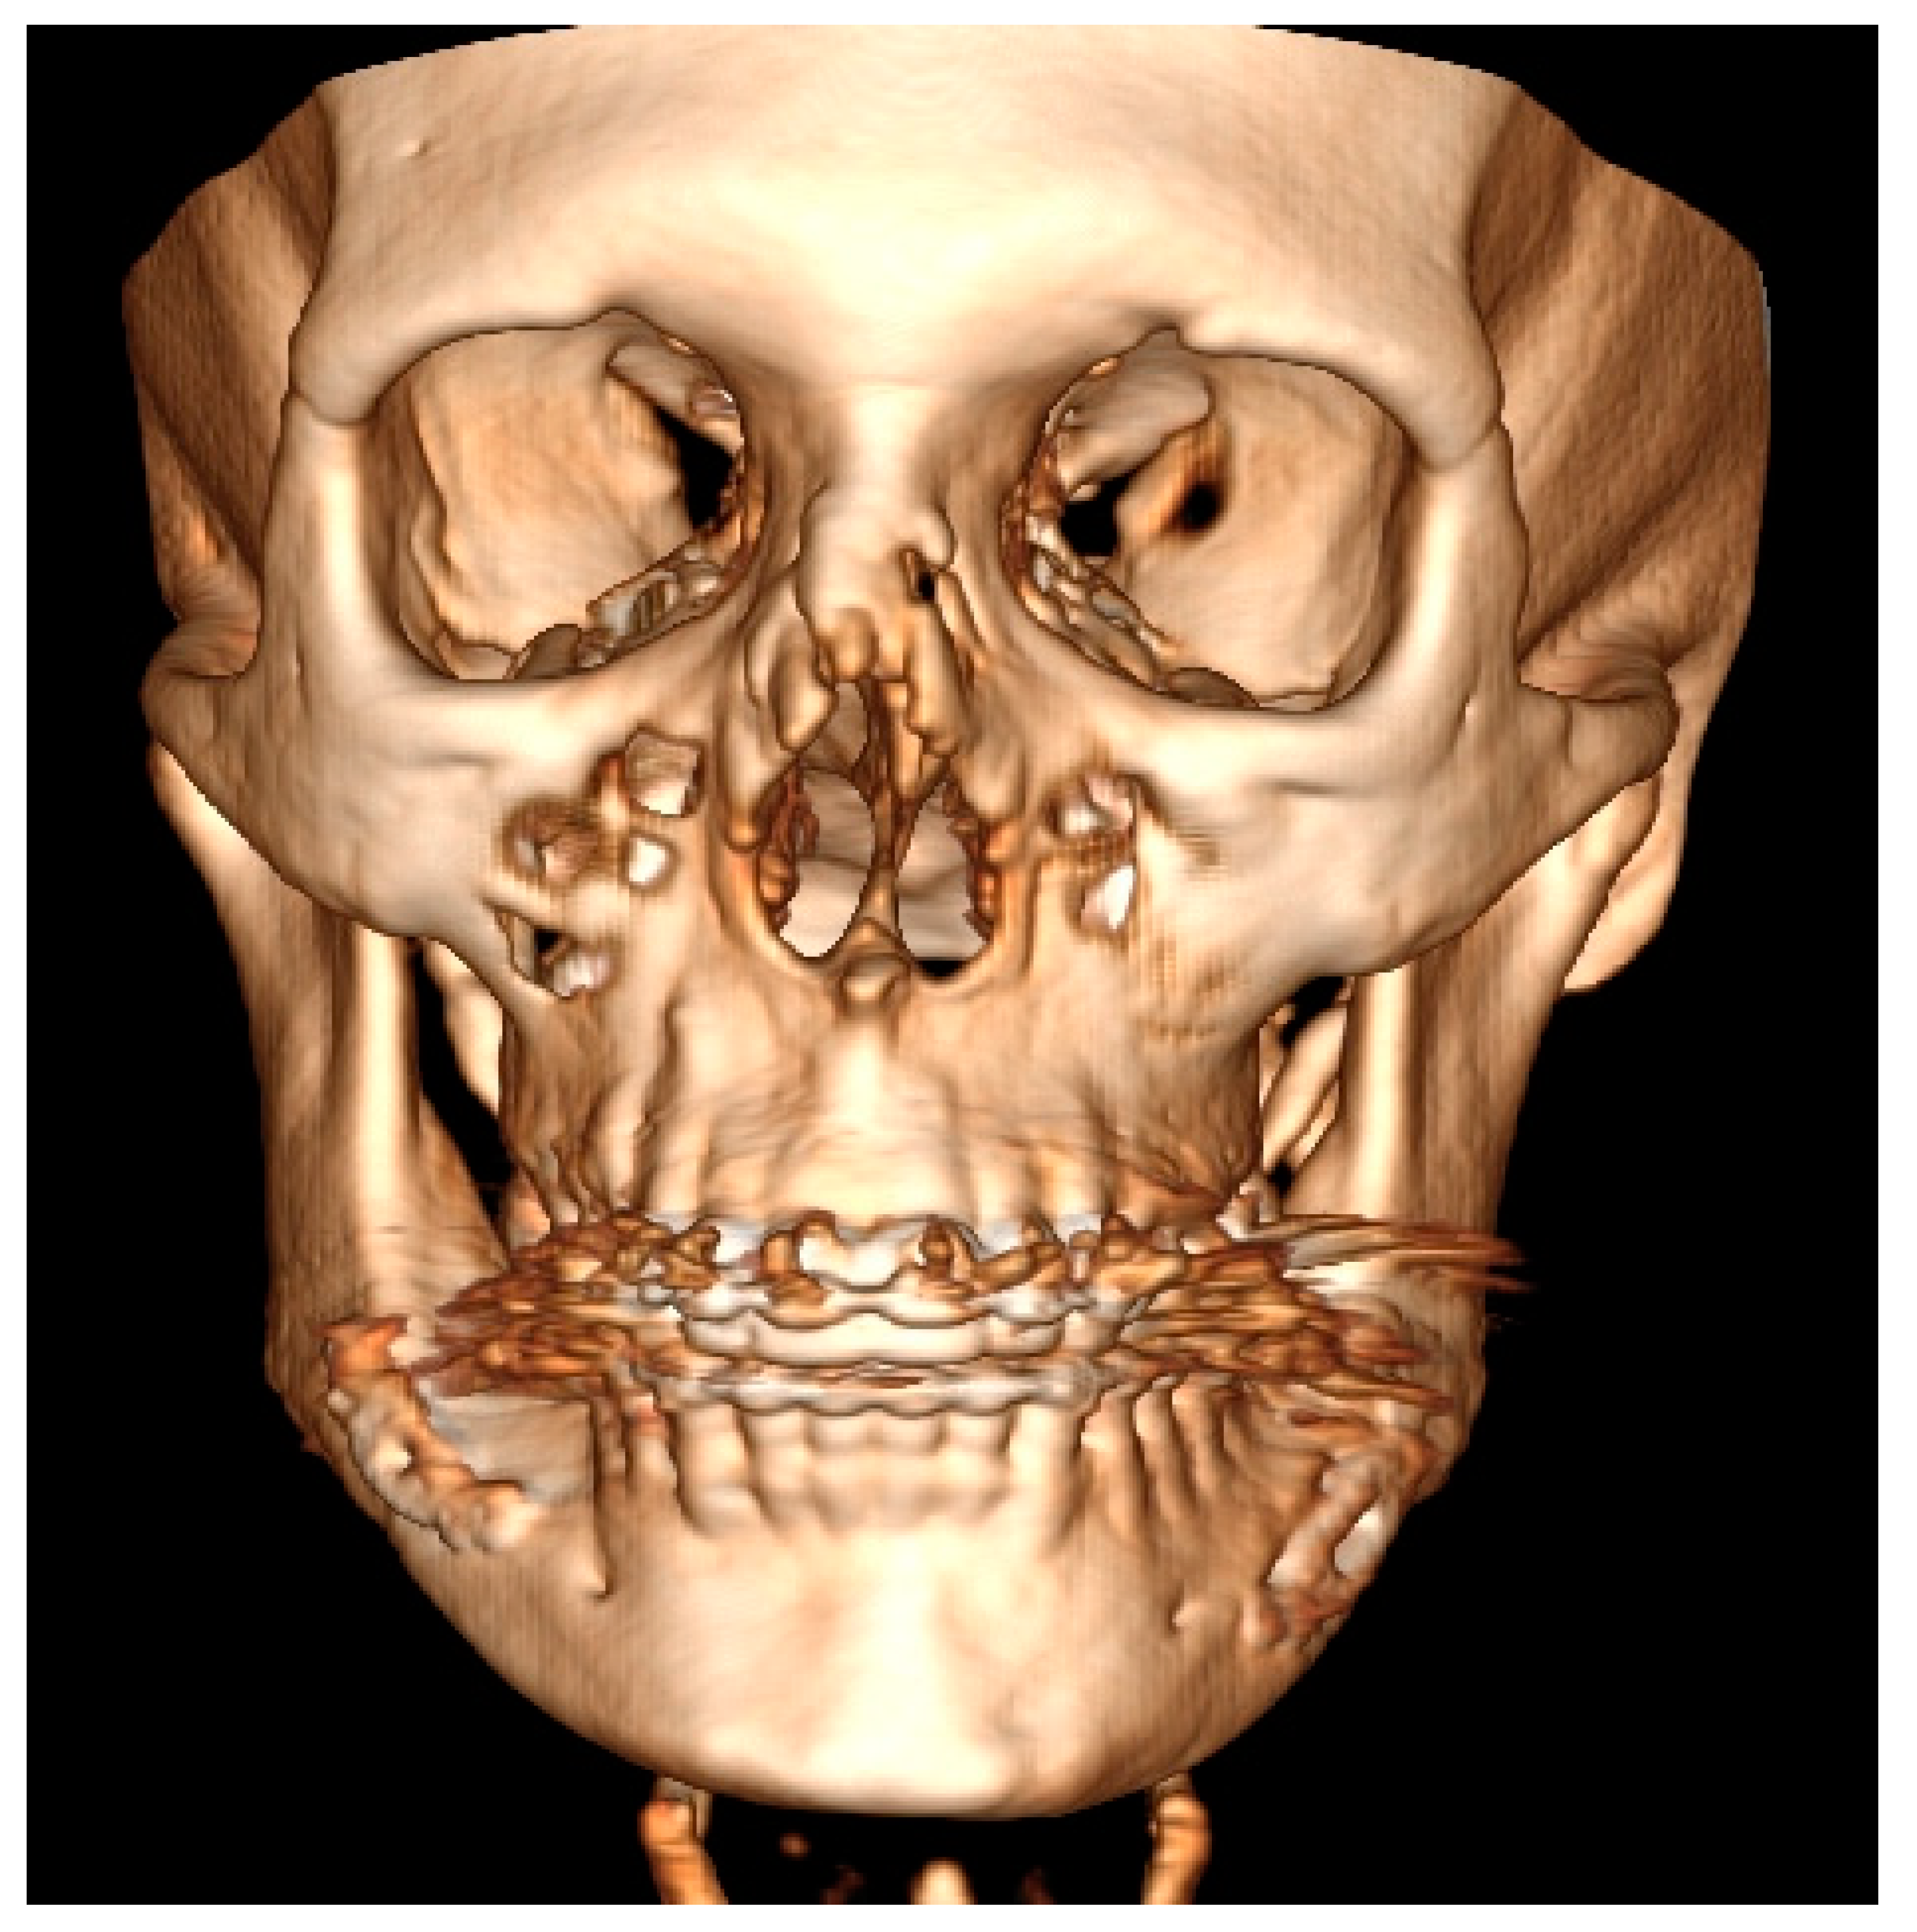

Figure 2.

Severe form of condylar hyperplasia.

The length between Go-Gn/Go-Gn and the vertical bone volume relation decreases the bone height on the opposite healthy side—the critical point of this technique is the distance between the Go-Go/Go-Gn position and the value of the F0-C bone index. In this case, approach 1C can be used with or without corrective angulotomy/anguloplasty, which reduces the angled volume on the affected side in vertical and horizontal dimensions. If both Go (Right) and Go (Left) are situated on the same horizontal line, no major surgery should be planned, unless performing a condylectomy might relocate the Go point on the affected side to a higher position afterward. Therefore, careful planning in the horizontal plane and the F5: Go measurement can help estimate whether any additional mandibular angle surgery should be planned (Figure 1 and Figure 2; Table 1). This was used in some of the authors’ cases where there was no maxillary bite-plane deviation, and no chin bone asymmetry was present.

The authors conclude that a very severe mandibular overgrowth with increased chin involvement should be a mandatory indication for the classic Ferguson approach with a surgical reduction in the mandibular angle on the affected side [7,13]. The main reason for this is the increased distance and height of the F0:F1 and F0:C:F0 values in this study (Figure 1). The authors fully agree with Ferguson’s approach, which is confirmed in the author’s measurements based on the suggested ARP: IM values and the distances between reference points in the presented study radiographs. Two different cases of one-sided mandibular overgrowths in hemimandibular hyperplasia are drawn and explained in Figure 2.